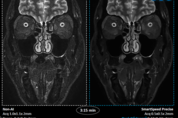

㈜필립스코리아는 자사 고유의 듀얼 AI 엔진 기반 MR 기술인 ‘스마트스피드 프리사이즈(SmartSpeed Precise)’를 공개했다. 이번 신기술은 자사 고유의 두 가지 AI 알고리즘을 적용해 의료진의 진단 워크플로우를 효율적으로 지원하고 고품질 영상을 제공함으로써 임상 진단 과정을 지원할 수 있도록 설계됐다. MRI(Magnetic Resonance Imaging, 자기공명영상)는 정밀 영상 진단 기술로, 중증 질환의 진단과 치료 결정 과정에서 중요한 역할을 하고 있다. 그러나 최근 만성 질환 환자가 늘어나면서 검사 수요 또한 빠르게 증가하고 있다. 이에 따라 더 빠른 속도, 높은 해상도, 방대한 데이터 처리에 대한 요구가 커지면서 이를 충족할 수 있는 의료 AI 기술에 대한 관심 역시 높아지고 있다. 필립스가 올해 발표한 ‘미래건강지수 2025 한국 보고서(Future Health Index 2025 South Korea report)’에 따르면, 국내 의료 전문가들은 AI 및 예측적 분석(predictive analytics)을 포함한 디지털 의료 기술이 ‘조기 개입을 통한 생명 구제(90%)’, ‘급성 또는 응급 의료 처치 감소(86%)’, ‘병원